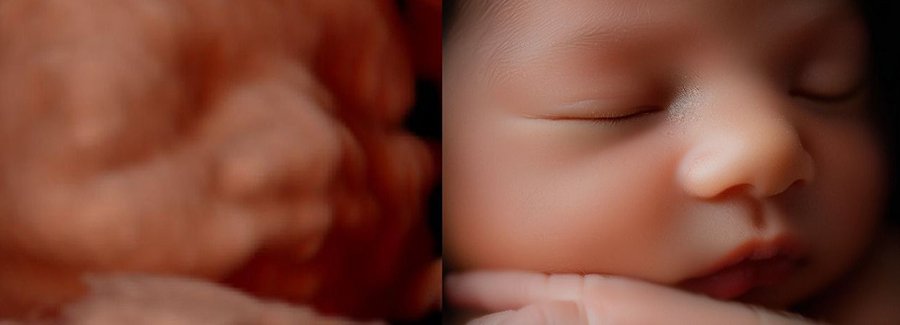

Often referred to as 5D, HD or FRV (fetal realistic view), 5D/HD is the newest development in pregnancy imaging. It captures and combines high definition volume data to create automated images with amazing color and clarity so you can see your baby as though you were looking from inside the womb.